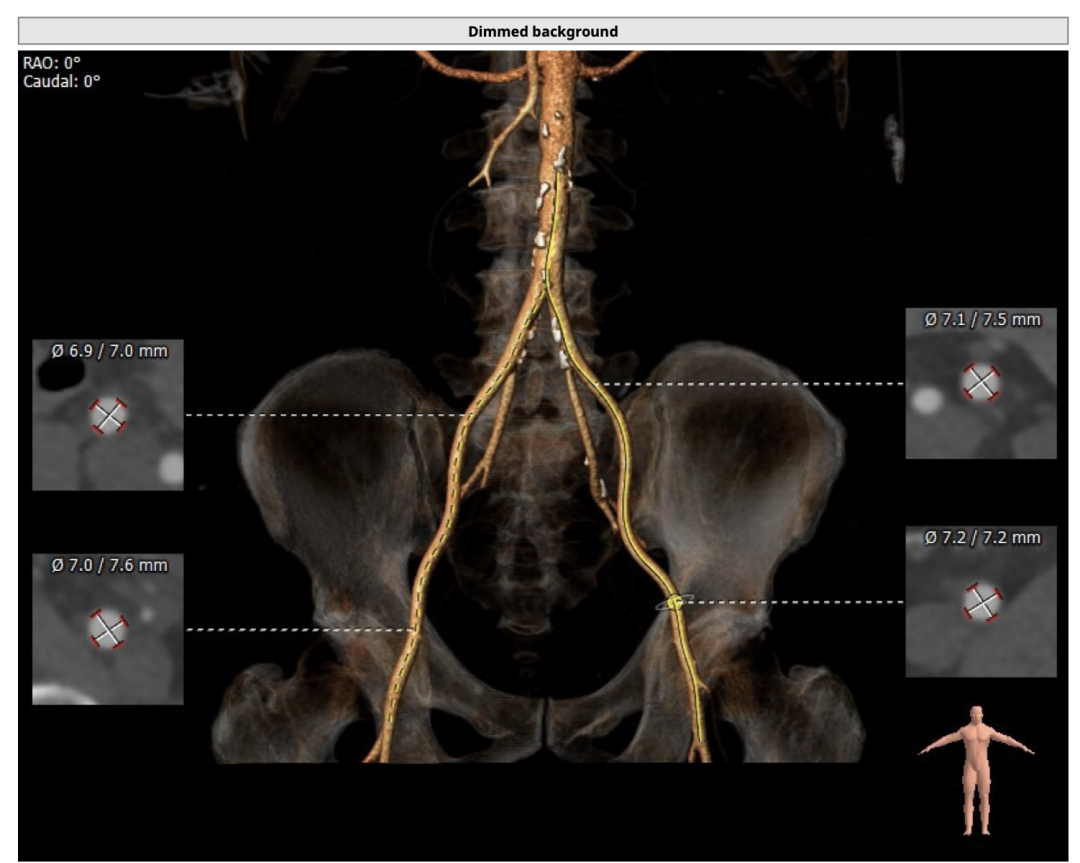

入路情况